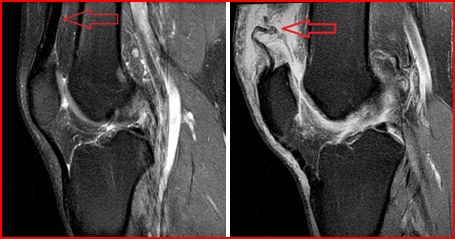

Lateral Collateral Ligament Tear Of The knee: Appearances On ...

With magnetic resonance imaging correlation, of acute lateral collateral ligament tear of the knee following trauma with findings on bone scintigraphy with single-photon emission tomography (SPET). The ated knee injuries to be identified which may not be evi- ... Access Document